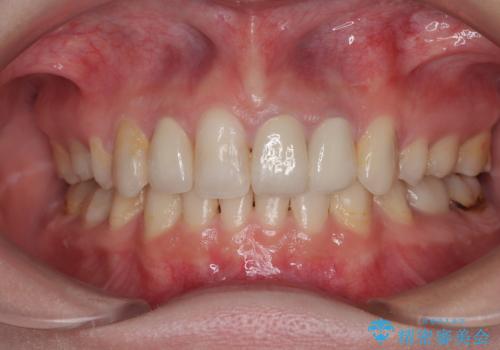

前歯綺麗にしたい。

変色してきた歯とプラスチックのクラウン オールセラミッククラウン治療